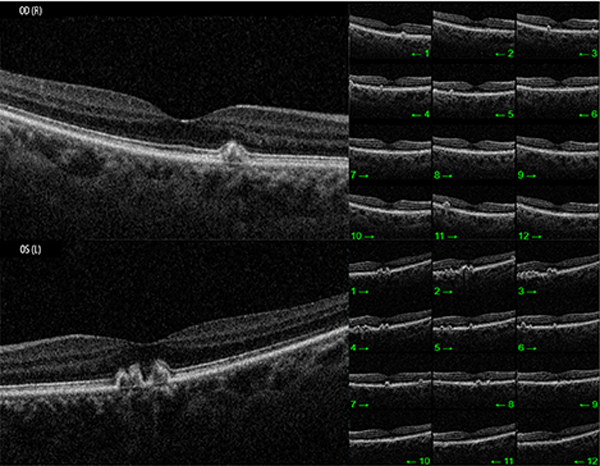

Ante estos hallazgos se continuó la evaluación con OCT que evidenció un perfil anterior macular conservado y una alteración del perfil posterior compatible con depósitos drusenoides a nivel del EPR (fig. 2) con mínima acumulación de líquido a nivel sub-EPR.

Figura 1. Fundus OCT ojo izquierdo y derecho respectivamente.

Figura 2. OCT macular de ojos derecho e izquierdo.